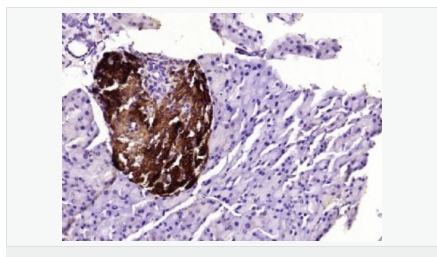

交叉反應(yīng):Human,Mouse,Rat(predicted:Pig,Horse,Rabbit) 推薦應(yīng)用:WB,IHC-P,IHC-F,ICC,IF,ELISA

產(chǎn)品應(yīng)用WB=1:500-2000 ELISA=1:5000-10000 IHC-P=1:100-500 IHC-F=1:100-500 ICC=1:100-500 IF=1:100-500 (石蠟切片需做抗原修復(fù))